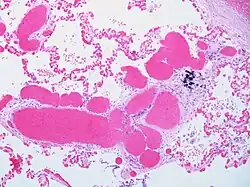

| Alveolar capillary proliferation as well as proliferation of larger blood vessels, probably venules. | |